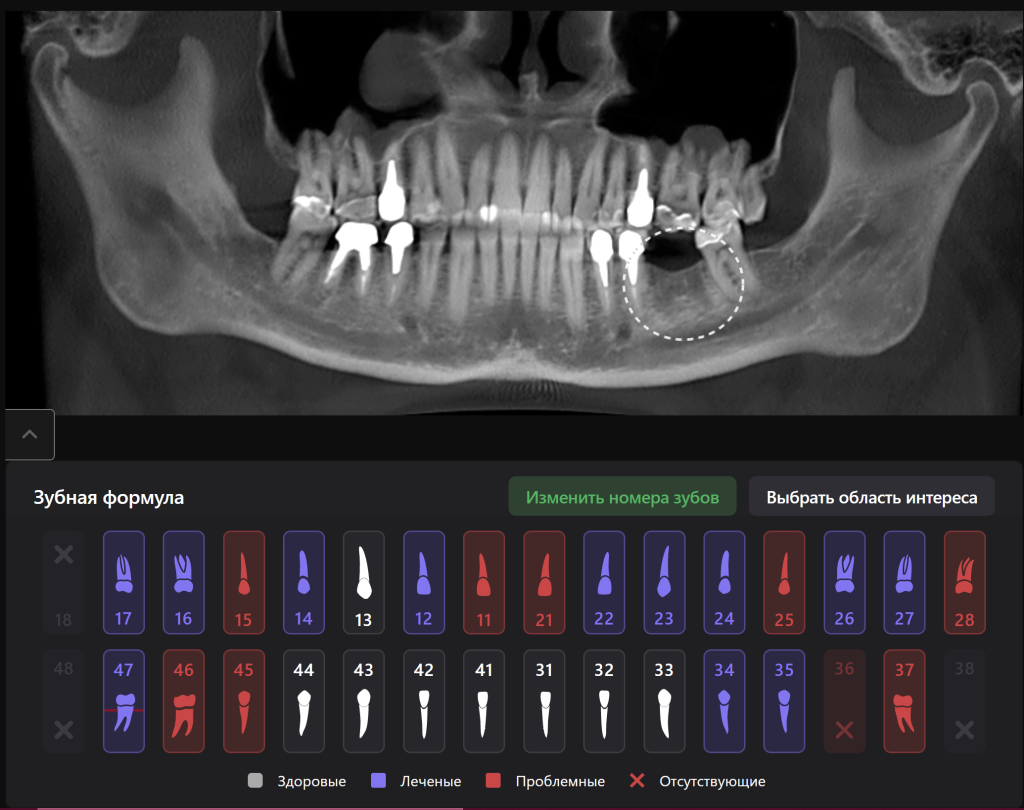

Представляем Вам клинический случай планирования имплантологического лечения вместе с искусственным интеллектом Diagnocat!

Интраоральная рентгенограмма, загруженная в FMX модуль Diagnocat демонстрирует благоприятную ортопедическую позицию имплантата